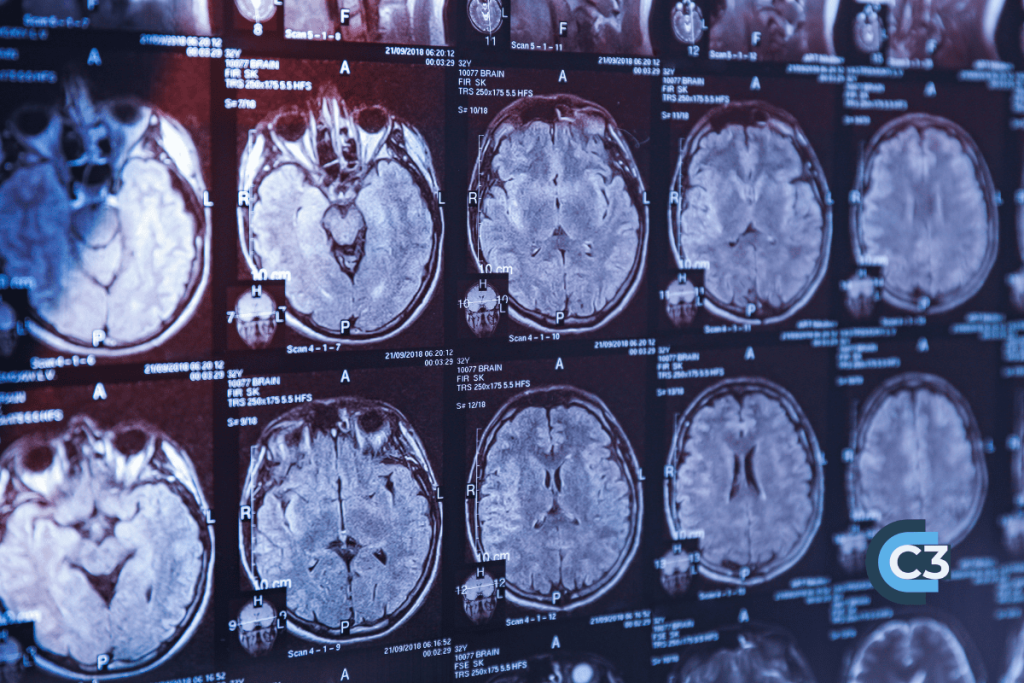

Specifically, a “concussion” is a mild traumatic brain injury (mTBI) and this is characterized by temporary neurologic dysfunction. Unfortunately, this type of injury is not visible with the standard enhanced imaging studies. This is why ambulance attendants will ask;

When Imaging Reveals a More Serious Injury

If imaging studies identify an epidural or subdural hematoma, these findings indicate a significant and potentially life-threatening injury. These conditions are distinct from concussions and demand urgent medical attention.